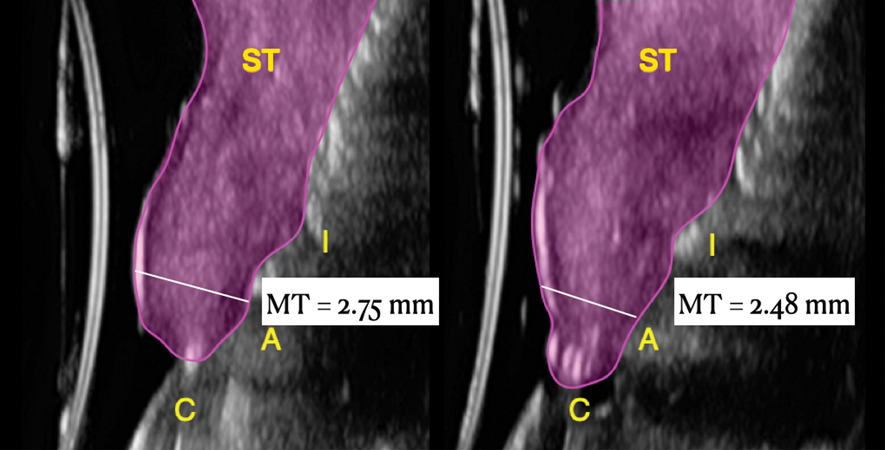

Ultrasonographic Assessment of Mucosal Thickness Gain

Previous studies have described in detail the ultrasound equipment setup and scanning procedures.7,13,15,16 A commercially available ultrasound imaging devicewas used with a 24-MHz miniature-sized transducer to obtain midfacial and interproximal scans at baseline and at 1-year follow-up. The transducer was oriented perpendicular to the occlusal plane and parallel to the implant's long axis to generate "B-mode" grayscale images. B-mode generates 2-dimensional grayscale images in which brightness is the result of the returned echo signal and its strength, which is dependent on the acoustical properties of the periodontal hard- and soft-tissue structures. The scans were saved in digital imaging and communications in medicine (DICOM) files and later exported into a software package, where mucosal thickness was measured 1.5 mm apical to the soft-tissue margin and found to be 0.97 mm and 0.74 mm at the right and left implants, respectively. After 12 months, the respective mucosal thickness was 2.75 mm and 2.48 mm. The soft-tissue thickness gain at the level of the right implant was 1.78 mm for the right implant, and 1.74 mm for the left implant.

This article has described the use of real-time, non-ionizing, high-frequency ultrasonography for assessing the increase in soft-tissue thickness and the anatomy of the peri-implant structures pretreatment and at the 1-year follow-up. The reliability and reproducibility of this technology has been shown in several clinical studies in which ultrasonography also was utilized to assess tissue perfusion after graft procedures and the levels of blood flow at healthy versus diseased implant sites.7,13,15,16,26,27 Ultrasonography enabled the observation of a substantial gain of mucosal thickness at 1 year, with the initial soft tissue (measured 1.5 mm apical to the soft-tissue margin) being 0.97 mm and 0.74 mm at the right and left dental implants, respectively, while the final mucosal thickness was 2.75 mm and 2.48 mm at the right and left dental implants, respectively. Considerable evidence supports the key role augmented gingival thickness plays in the stability of the soft-tissue margin in natural dentition,17,28 and it is reasonable to assume that this concept also may be valid at implant sites.13 The benefits of soft-tissue phenotype modification, in terms of increased keratinized mucosa and mucosal thickness, also include patient-reported outcomes and implant health-related parameters.29

Fig 19. Ultrasonographic comparison of the volumetric gain obtained with the intervention. Fig 19: Baseline. Fig 20: 1-year post-treatment. “C” identifies the crown, “A” the abutment, “I” the implant fixture, and “ST” the soft tissue. The soft tissue at baseline (Fig 19) is highlighted in blue, while the soft tissue at the 1-year follow-up (Fig 20) is shown in purple. Mucosal thickness (“MT”) at baseline (Fig 19) and at 1 year (Fig 20) is also displayed. (In both figures, the left panel is implant No. 8 midfacial, and the right panel is implant No. 9 midfacial.)

Figure 19

Fig 20. Ultrasonographic comparison of the volumetric gain obtained with the intervention. Fig 19: Baseline. Fig 20: 1-year post-treatment. “C” identifies the crown, “A” the abutment, “I” the implant fixture, and “ST” the soft tissue. The soft tissue at baseline (Fig 19) is highlighted in blue, while the soft tissue at the 1-year follow-up (Fig 20) is shown in purple. Mucosal thickness (“MT”) at baseline (Fig 19) and at 1 year (Fig 20) is also displayed. (In both figures, the left panel is implant No. 8 midfacial, and the right panel is implant No. 9 midfacial.)

Figure 20